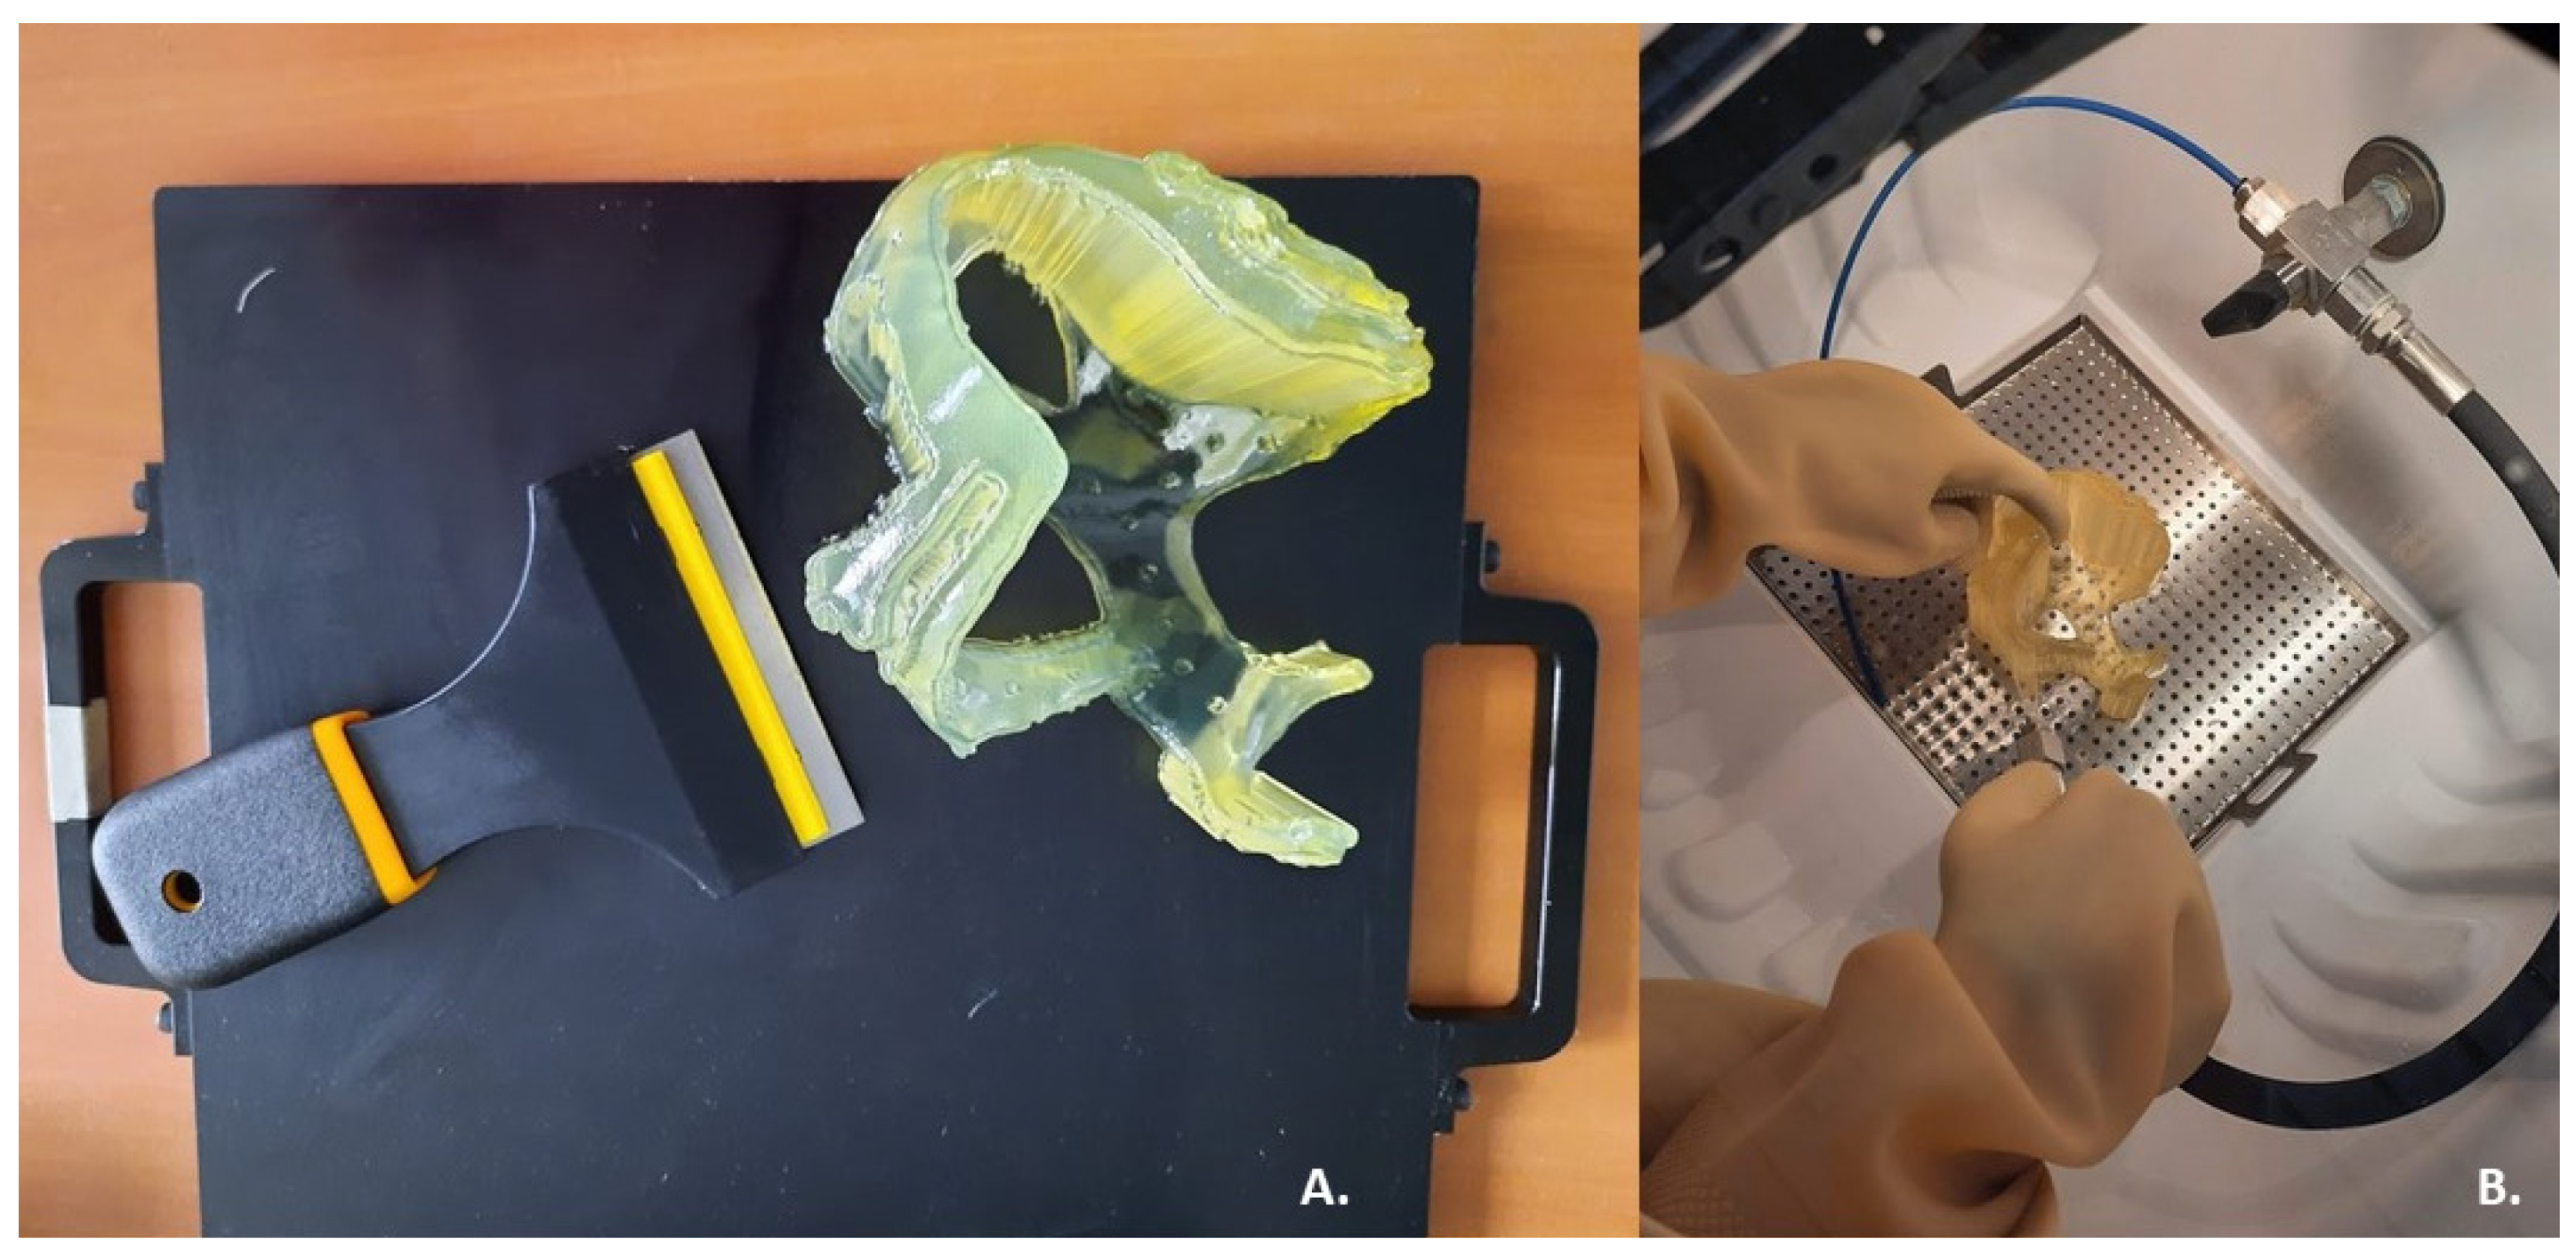

2.3. 3D Printing

3. Results